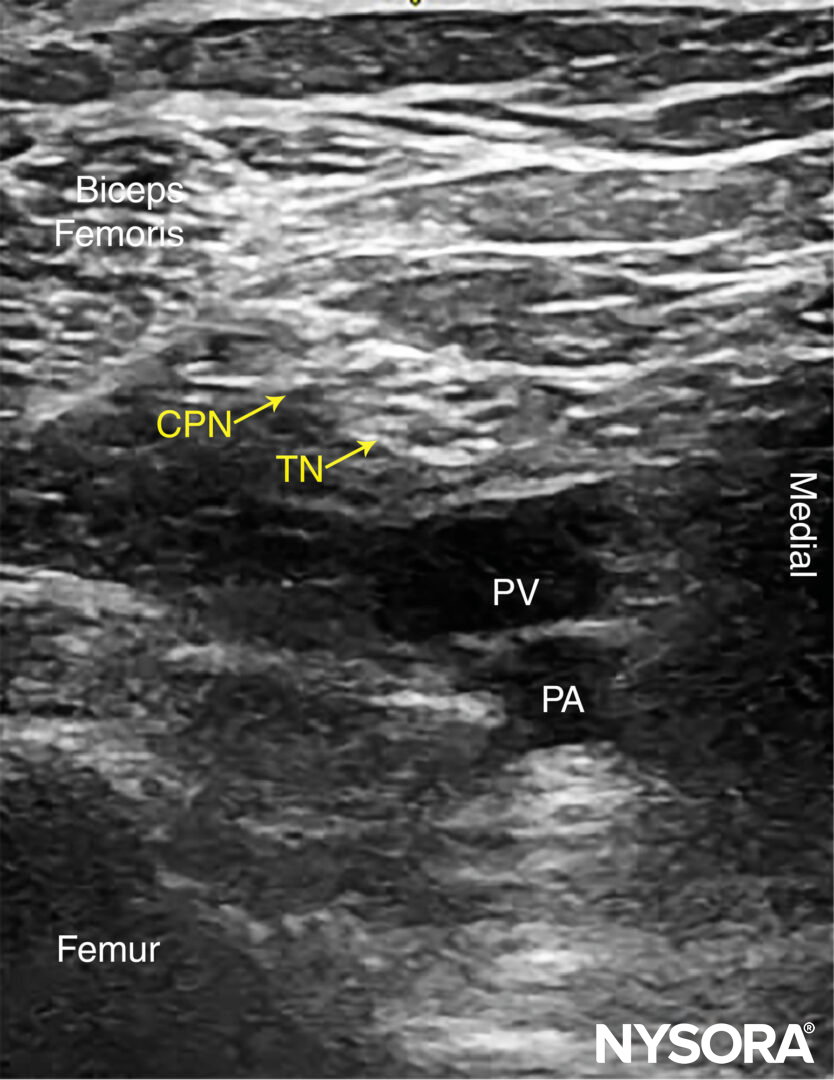

The anatomy of the sciatic nerve in the popliteal fossa is variable, and the division into the tibial nerve (TN) and common peroneal nerve (CPN) occurs at an inconstant distance from the popliteal crease (Figure 1). With nerve stimulator–based techniques, larger volumes (eg, > 40 mL) of local anesthetic have been used to increase the chance of nerve block success.

FIGURE 1. Cross-sectional anatomy of the sciatic nerve in the popliteal fossa. Shown are the common peroneal nerve (CPN), tibial nerve (TN), popliteal artery (PA), popliteal vein (PV), femur, biceps femoris muscle (BFM), semimembranosus muscle (SmM), and semitendinosus (StM) muscle.

Beginning with the transducer in the transverse position at the popliteal crease, the popliteal artery is identified, aided with color Doppler US when necessary, at a depth of approximately 3–4 cm. The popliteal vein accompanies the artery at it is positioned just superficial (posterior) to it. On either side of the artery are the biceps femoris muscles (laterally) and the semimembranosus and semitendinosus muscles (medially). The tibial nerve is positioned superficial and lateral to the vein and is seen as a hyperechoic, oval or round structure with a honeycomb pattern (Figure 3). Asking the patient to dorsiflex and plantar flex the ankle makes the two sciatic nerve branches twist or move in relation to each other. Usually, tilting the transducer caudally is necessary to bring out the nerve from the neighboring adipose tissue.

FIGURE 3. Sonoanatomy of the sciatic nerve at the popliteal fossa. The two main divisions of the sciatic nerve, the tibial nerve (TN) and the common peroneal nerve (CPN), are seen immediately lateral and superficial to the popliteal vein (PV) and artery (PA). This image was taken at 5 cm above the popliteal fossa crease, where the TN and CPN have just started diverging.